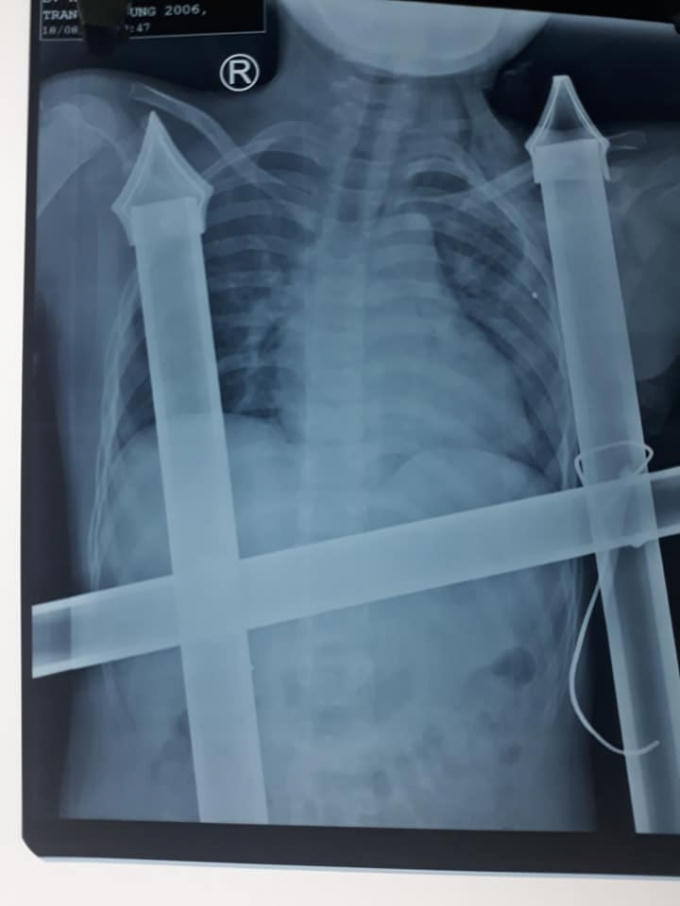

Hình ảnh chụp Xquang cho thấy thanh kim loại xuyên sâu vào ngực bé trai.

Thanh hàng rào có đầu sắc nhọn đâm xuyên cơ thể. Phát hiện sự việc người thân vô cùng hoảng sợ. Ngay sau đó, một phần hàng rào sắt được khẩn trương cắt rời để đem cậu bé đi cấp cứu. Bệnh nhi với tấm hàng rào kim loại dính chặt trên cơ thể được đưa đến bệnh viện, trong đó phần cọc sắt sắc nhọn dài hơn 10cm đã xuyên dọc thành ngực trái bệnh nhân. Khẩn trương sơ cứu ban đầu, bệnh nhân được chuyển mổ cấp cứu.

Qua hình ảnh phim Xquang, xác định vết đâm của ngạnh sắc nhọn hàng rào đã chạm tới nền sọ của bệnh nhân. Êkip phẫu thuật cố gắng tháo đầu sắc nhọn này, và sẵn sàng xử lý các tình huống tổn thương các mạch máu lớn, gây nên tình trạng chảy máu ồ ạt, đe dọa tính mạng của bệnh nhi ngay trên bàn mổ. Tuy nhiên, rất may mắn là vật sắc nhọn không làm mạch máu lớn và nội tạng bị tổn thương. Bệnh nhân bị đứt cơ ngực lớn, cọc sắt hàng rào tạo nên đường hầm trong khoang ngực kéo dài trên 10cm.